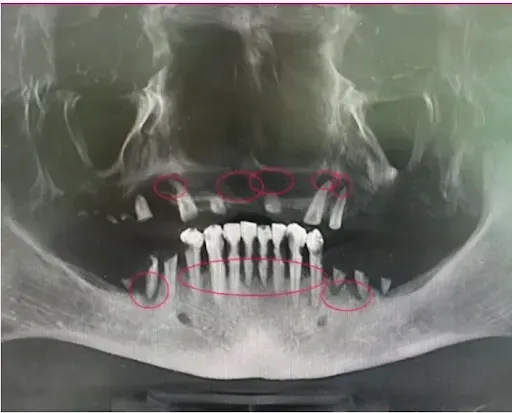

The scan below shows you a mouth with severe infection. The infection is circled. In fact, there was so much infection on the upper jaw which had been there for so long, this person was no longer a candidate for dental implant treatment and was confined to a denture.